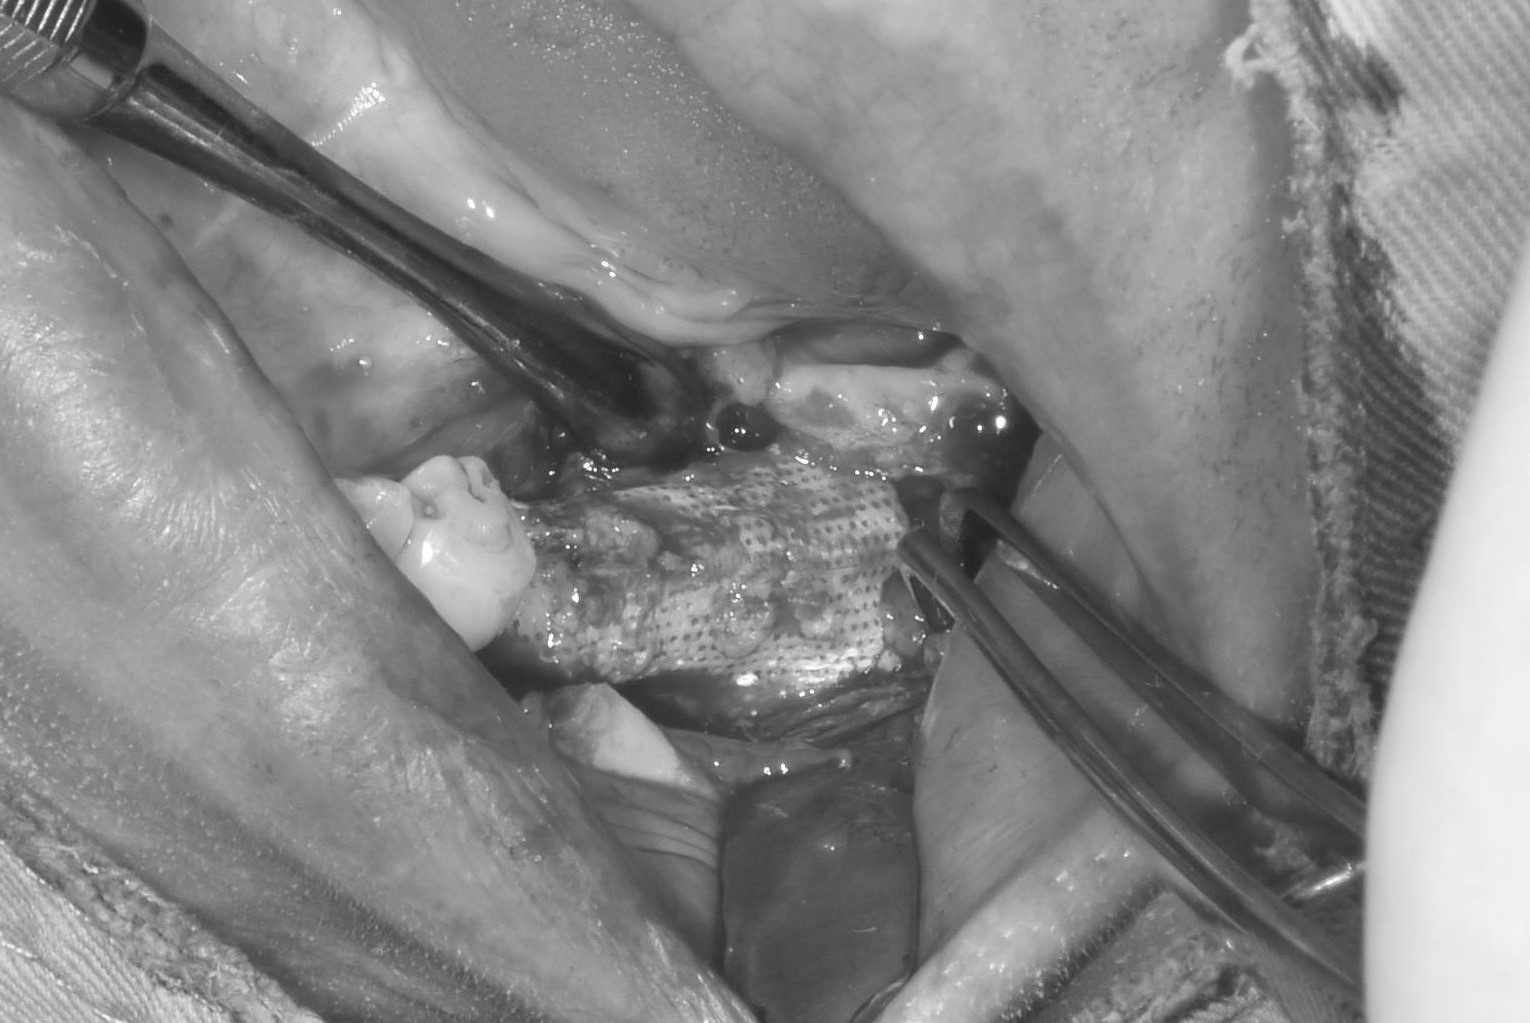

案例四

翻瓣補骨的區域,先擷取所需不可吸收骨膜的大小,用骨釘固定

*不可吸收骨膜:不會被身體吸收、需要再開刀取出的膜,放在補骨區用來隔離軟組織並撐住空間,讓骨粉有足夠時間生長成新骨

補入所需骨粉